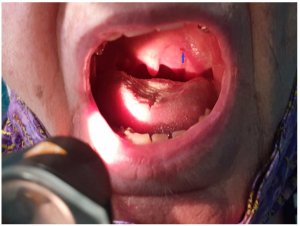

Diagnostic par image – quiz n°13